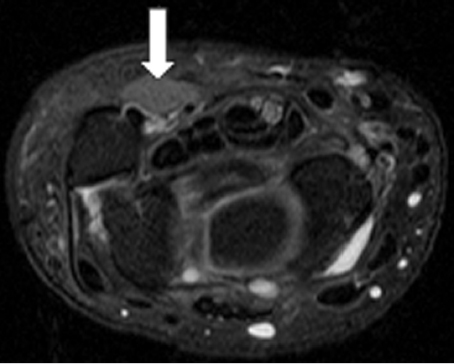

Ulnar tunnel syndrome has been well-described in the literature and might be the result of various causes, including ganglia 8 , 9 , 10 , 11 (as depicted in ► Fig. 26.4), fractures or dislocations of the ulnar side of the wrist, 9 , 12 , 13 anomalous muscle bellies or fibrous bands, 11 , 14 , 15 (as shown in ► Fig. 26.5), hemangiomas, 16 bipartite hamate, 17 giant cell tumors, 18 thrombosis of the ulnar artery, 9 , 11 , 19 osteoarthritis of the distal radioulnar joint and carpal joints, 20 , 21 rheumatoid tenosynovitis, 22 other benign soft tissue masses (shown in ► Fig. 26.6), bicycle racing, and other activities that require either prolonged wrist hyperextension or continuous pressure on the hypothenar eminence. 16 More recently, with the extreme popularity of indoor cycling classes, we have seen an increased prevalence of this condition which is termed cyclers’ palsy.